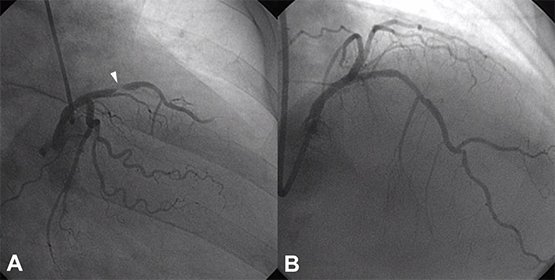

The patient had a critical 99 percent stenosis in the middle left anterior descending artery with TIMI 2 flow. He underwent a coronary stent placement. Subsequent post MI and arrest care was provided by the Cardiology Critical Care team including hypothermia protocol. Thirty-six hours later he was rewarmed, and made an excellent recovery without any neurologic sequelae. A few days later, he was discharged home in stable condition with a complete recovery.

A: Coronary angiogram with tight 99% Mid LAD stenosis (white arrow). B: The same vessel after Transradial PCI.